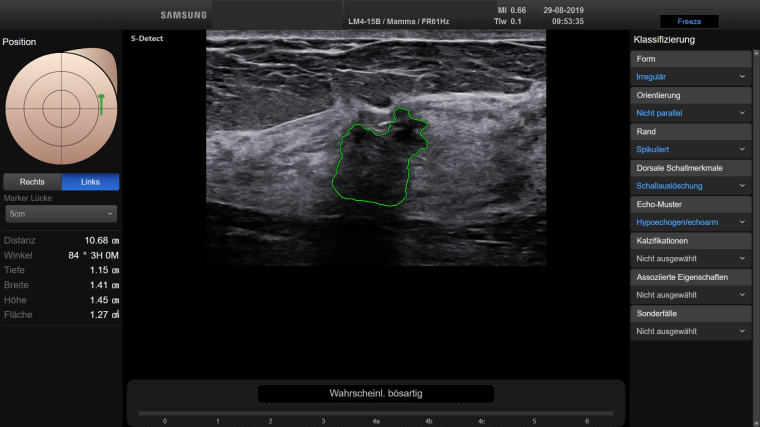

Duda: Während auf mammografischer Seite schon lange CAD-Systeme (Computer Aided Diagnosis) im Gebrauch sind, schien auf dem Gebiet des handgeführten Ultraschalls eine Unterstützung durch KI-Systeme (virtuelle oder künstliche Intelligenz) lange Zeit unrealistisch. Mit der jetzt verfügbaren Funktion des S-Detect im RS85 Ultraschallsystem der Firma Samsung können aber unklare Befunde im Sonogramm automatisch analysiert werden. Das Programm zeigt ohne Vorgabe des Untersuchers verfügbare Umrisse und macht Vorschläge zur Beschreibung und zur Dignitätseinstufung (Abb. 1 und 2). Diese Zusatzfunktion ist sekundenschnell verfügbar und gibt dem Untersucher eine zusätzliche Sicherheit bei schwierigen Befunden, aber beispielsweise auch bei Therapiekontrollen.